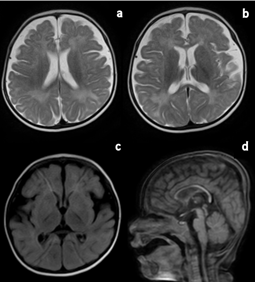

Figure 1 Rasmussen’s encephalitis.

Axial T2 (a) and FLAIR (b) weighted image of a 3-year-old child with a history of perinatal hypoxia and developmental delay shows marked diffuse left cerebral hemiatrophy with dilated left ventricle, encephalomalacia, gliosis, and subcortical cystic changes suggestive of Rasmussen’s encephalitis.

FLAIR, fluid-attenuated inversion recovery.